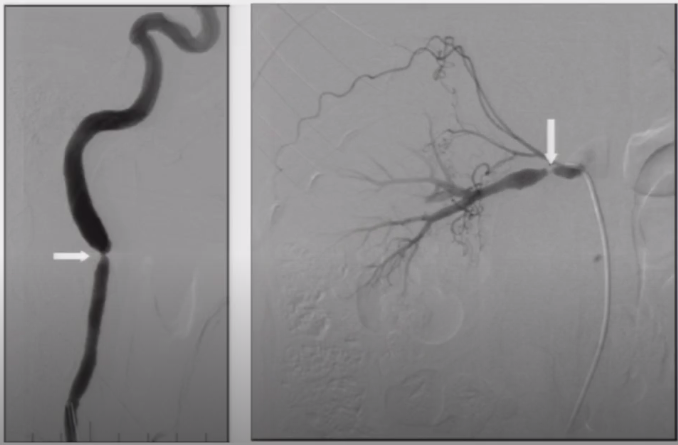

图1 内膜纤维组织增生型

图2 中膜纤维组织串珠样改变(肾动脉、颈动脉)

➤ 中膜纤维组织增生的典型表现——串珠样狭窄改变

图7 55岁女性,表现为难以控制的高血压,肾动脉和颈内动脉中-远段呈串珠样狭窄改变,串珠直径大于正常血管腔